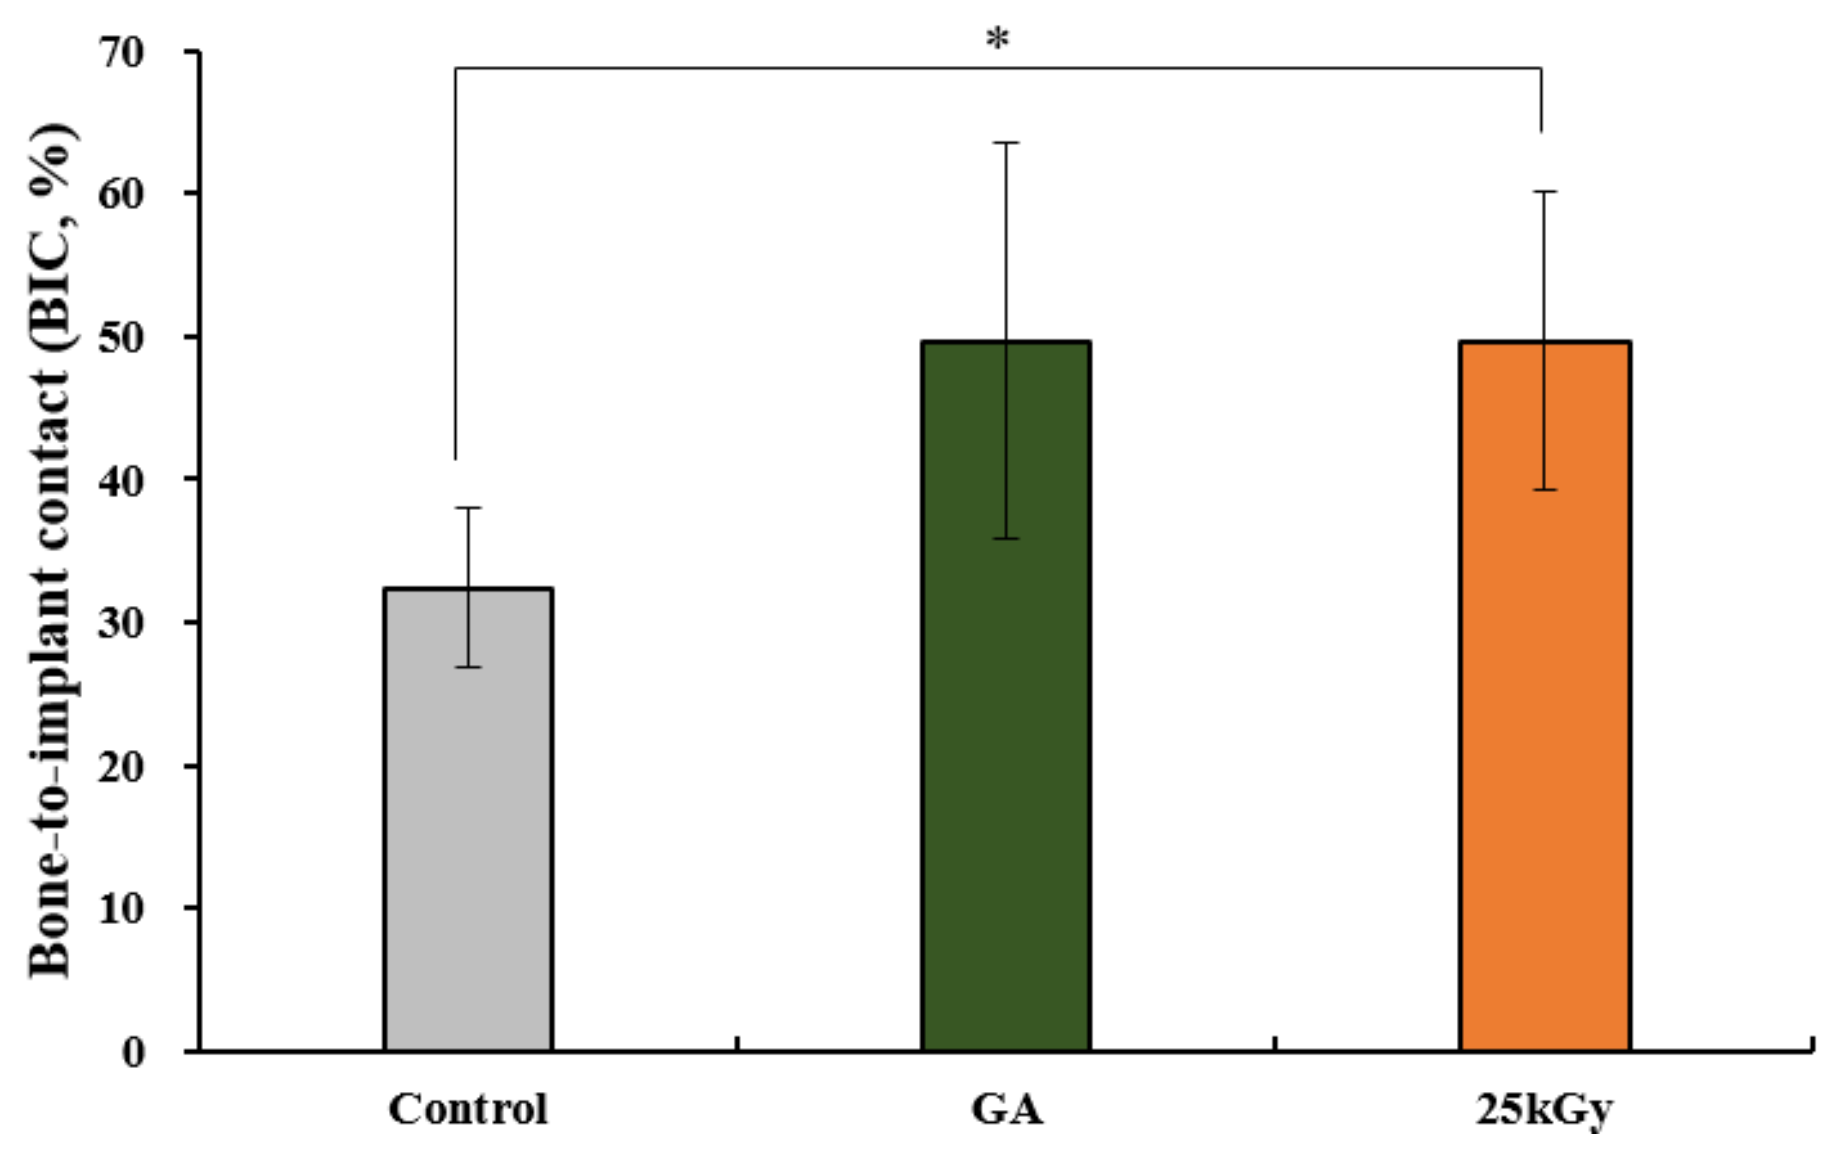

2.2.4. Histometric Findings

4.4. Statistical Analysis